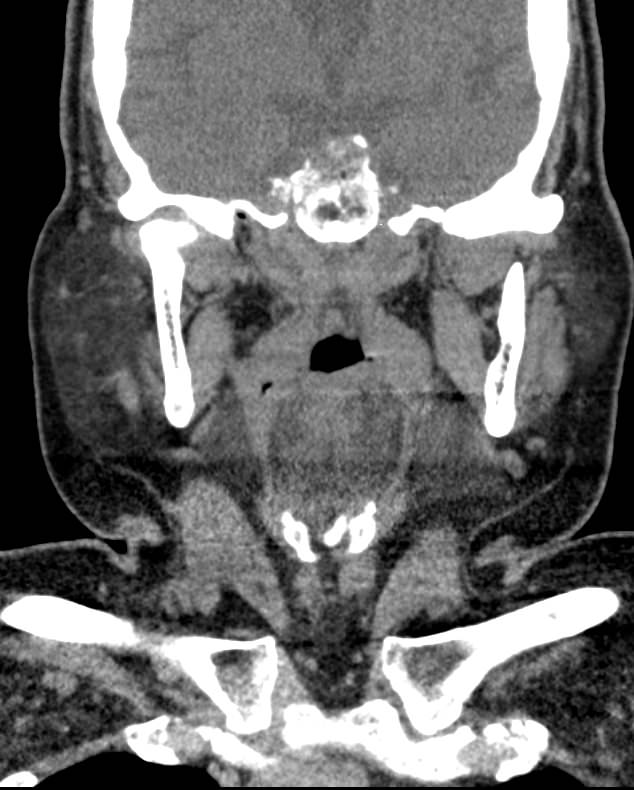

Мультиспиральная компьютерная томография – это высокоинформативный лучевой метод диагностики различной патологии мягких тканей шеи, включая воспалительные заболевания, травматические повреждения и опухолевые процессы. КТ позволяет оценить состояние щитовидной железы, паращитовидных желез, гортани, верхней части пищевода, шейных лимфоузлов и окружающих мягких тканей.

Метод КТ основан на применении рентгеновского излучения. Однако в отличие от обычного рентгена, при котором снимки производятся в одной плоскости, при КТ излучатель рентгеновских лучей постоянно двигается вокруг объекта исследования, проводя сканирование в различных плоскостях, а затем трансформируя полученные данные в цифровые трехмерные изображения. Это дает возможность визуализировать органы и ткани в мельчайших подробностях, а с помощью объемных 3D-реконструкций наглядно оценить пространственное расположение органов и патологических образований.

Рентгеновские лучи лучше всего поглощаются плотными структурами, такими как костная ткань. Поэтому кости хорошо видны на снимках КТ. Это делает компьютерную томографию незаменимой при необходимости обследования, в частности, костного скелета гортани. Однако для улучшения визуализации мягких тканей требуется введение специального контрастного препарата, поэтому КТ мягких тканей шеи в подавляющем большинстве случаев проводится с контрастным усилением.

Для контрастирования используется йодсодержащее контрастное вещество, которое в составе рентгеноконтрастного препарата вводится в вену пациенту непосредственно во время исследования. Благодаря способности контраста поглощать рентгеновские лучи на снимках КТ хорошо контрастируются кровеносные сосуды и опухолевые образования, имеющие, как правило, развитую сосудистую сеть. Методика внутривенного болюсного контрастирования помогает обнаружить воспалительные изменения, отличить доброкачественные опухоли от злокачественных, выявить поражение лимфатических узлов и степень прорастания опухоли в магистральные сосуды и окружающие ткани.